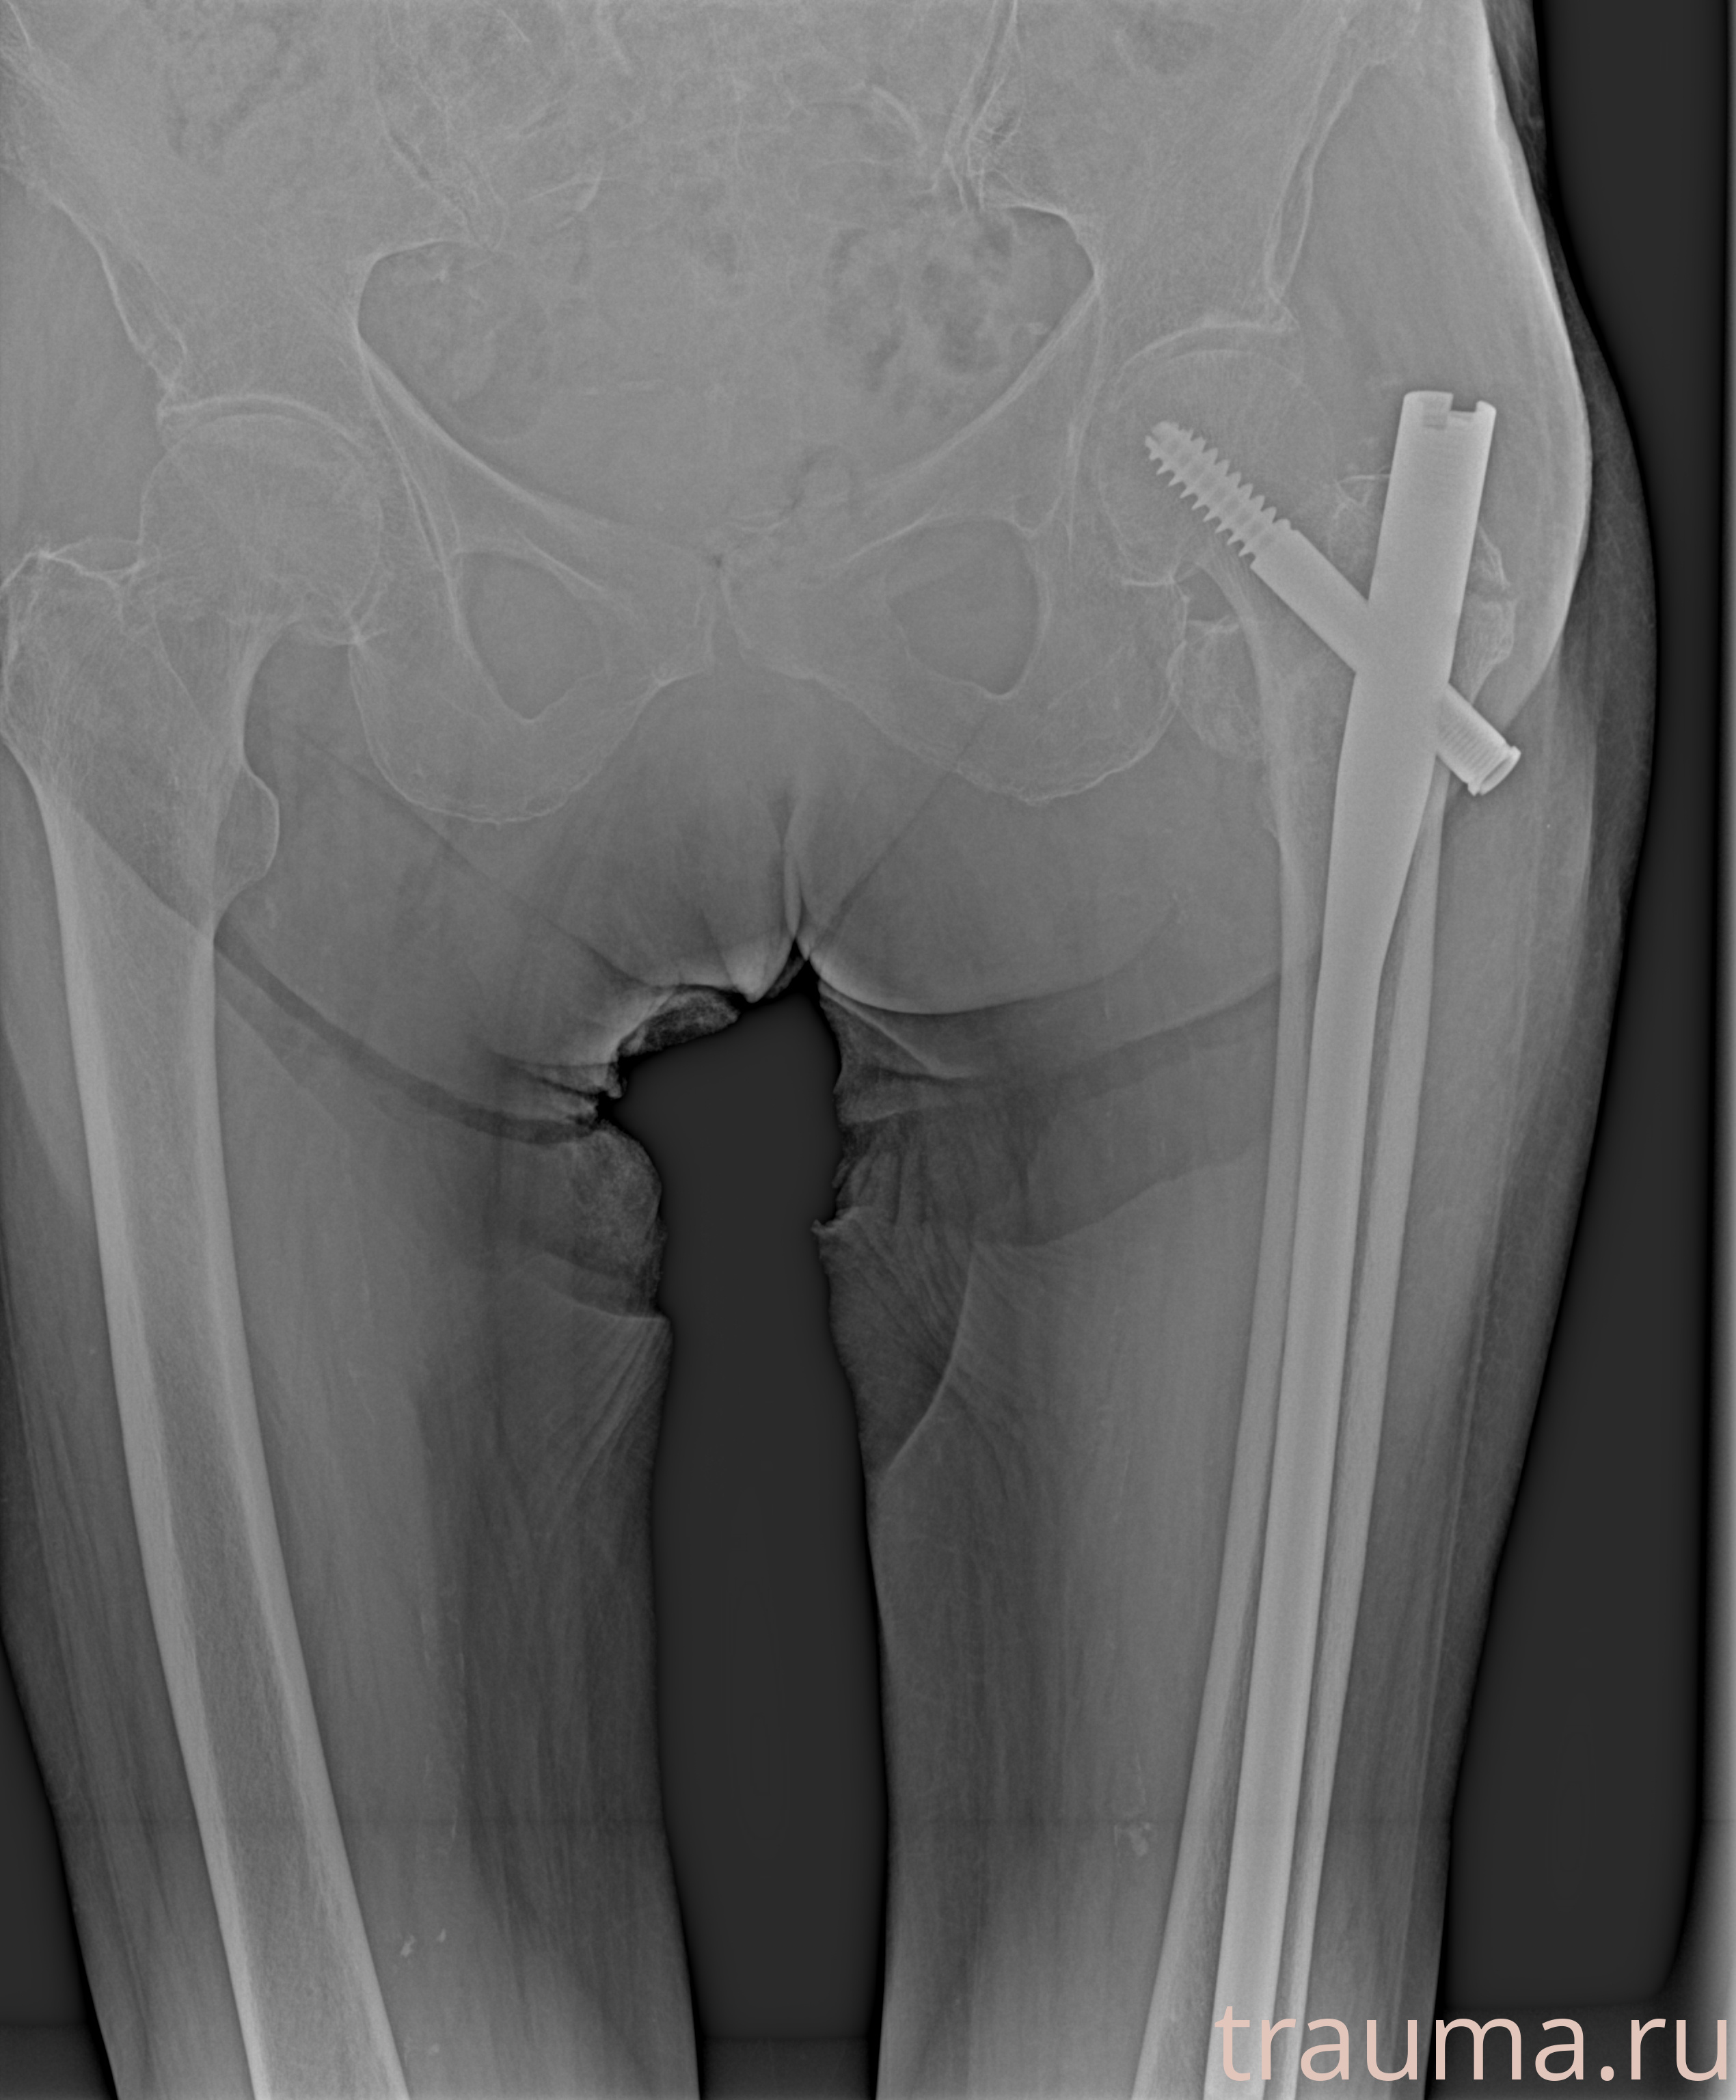

Рентгенограммы

Рентген на дому: по вашему адресу приезжает врач-рентгенолог, травматолог-ортопед с мобильным рентгеновским аппаратом, проводит диагностику травмы или заболевания, делает необходимые рентгенограммы, дает рекомендации по дальнейшему лечению. Получить качественные снимки в домашних условиях возможно благодаря уникальной методике, разработанной МосРентген Центром для института  Склифосовского